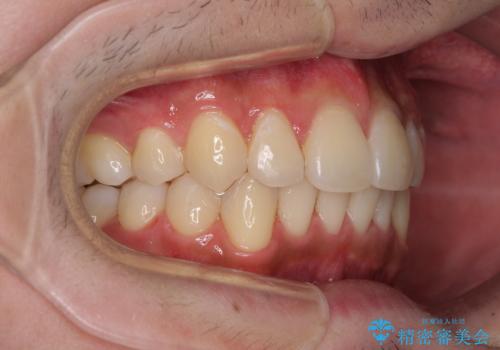

矯正治療の後戻りをインビザライン・ライトで解消

- 矯正治療の後戻りを気にして来院された患者様です。

後戻りは軽微であったので、インビザライン・ライトにより矯正治療を行うこととしました。

インビザライン・ライトは提供されるマウスピースの数に制限があり、通常のタイプよりもマウスピース提供期間が短くなっている一方、安価に治療を行うことができるプランです。

治療のゴールも変更できないため、軽微な歯列不正や、後戻り改善などに適しています。